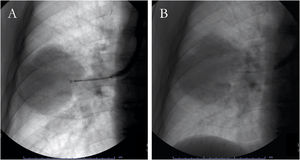

Peripheral lung lesionsA transbronchial biopsy is performed when the lesion cannot be directly assessed with the bronchoscope: it is wedged in the bronchus pertaining to the anatomical site of the lesion, and the closed forceps are pushed in the peripheral area of the lung, opened at 5...6...mm from the lesion and then closed to collect sample (Fig. 1A).6 Fluoroscopy guidance can improve the sensitivity in case of peripheral focal and diffuse cancer lesions.6,76,77 Observational studies have demonstrated that navigational methods (i.e., electromagnetic navigation bronchoscopy, radial probes ultrasounds, virtual bronchoscopy) and/or ultrathin instruments may increase the diagnostic yield of conventional, fluoroscopy-guided technique (77...84%).44,78...80

Peripheral pulmonary lesionsTransbronchial needle aspiration with the guidance of fluoroscopy has been adopted to sample peripheral lung lesions (both nodules and masses) since 1984 (Fig. 1B).42 A recent systematic review and meta-analysis showed a diagnostic yield of 53% and a rate of complications <9%, with pneumothorax and bleeding being the most frequent events.43 Several clinical and procedural variables may affect its accuracy: CT bronchus sign, an underlying malignant process, diameter of the lesions >3...cm, and ROSE employment are the most important predictive factors of a positive aspirate (Table 2). Notably, data on comparison between TBNA and transbronchial forceps biopsy (TBB) in studies where both procedures were performed in the same patients showed a significant diagnostic advantage when TBNA is performed (diagnostic yield: 60% vs. 45%, respectively), although studies have shown that TBNA is still a underused sampling technique.43,44